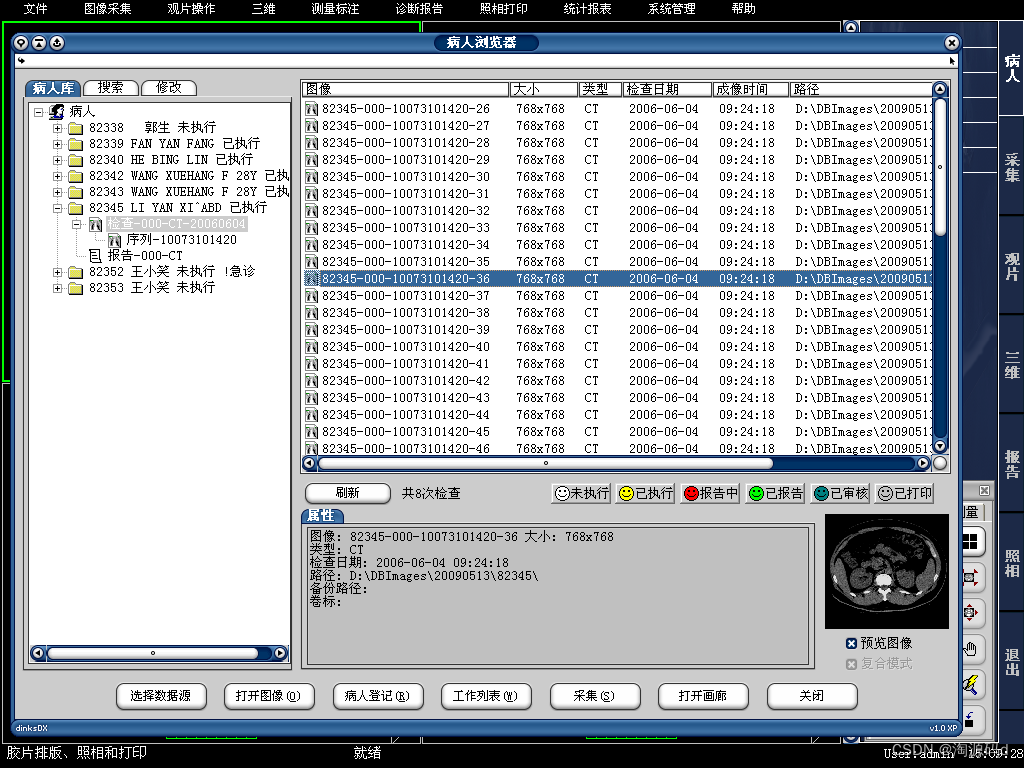

PACS系统源码 可与医院HIS、LIS无缝连接

PACS系统以实现医学影像数字化存储、诊断为核心任务,从医学影像设备(如CT、CR、DR、MR、DSA、RF等)获取影像,集中存储、综合管理医学影像及病人相关信息,建立数字化工作流程。

系统可实现检查预约、病人信息登记、计算机阅片、电子报告书写、胶片打印、数据备份等一系列满足影像科室日常工作的功能,并且由于影像数字化存储,用户可利用影像处理与测量技术辅助诊断、方便快捷地查找资料或利用网络将资料传输至临床科室,还可与医院HIS、LIS无缝连接,使得医院内部信息高度共享,同时也为远程医疗奠定了基础,极大提高工作效率。

PACS系统模块内容

图像采集系统

科室预约登记系统及报表系统